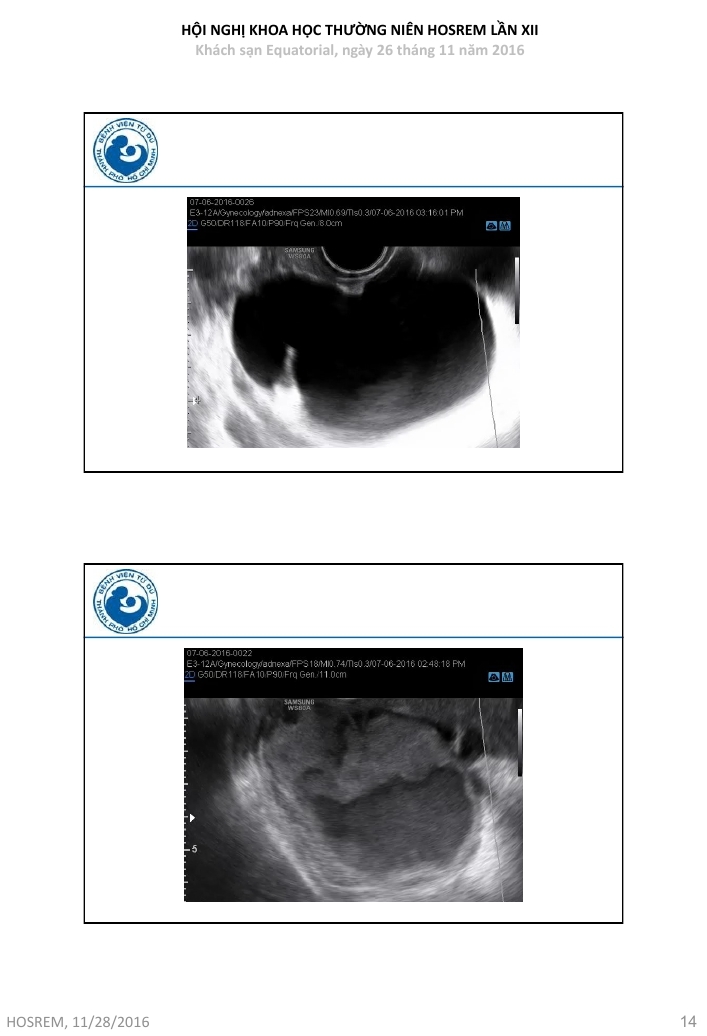

Ung thư buồng trứng  chẩn đoán và đánh giá nguy cơ ác tính theo IOTA

Từ khóa: Ung thư buồng trứng chẩn đoán và đánh giá nguy cơ ác tính theo IOTA